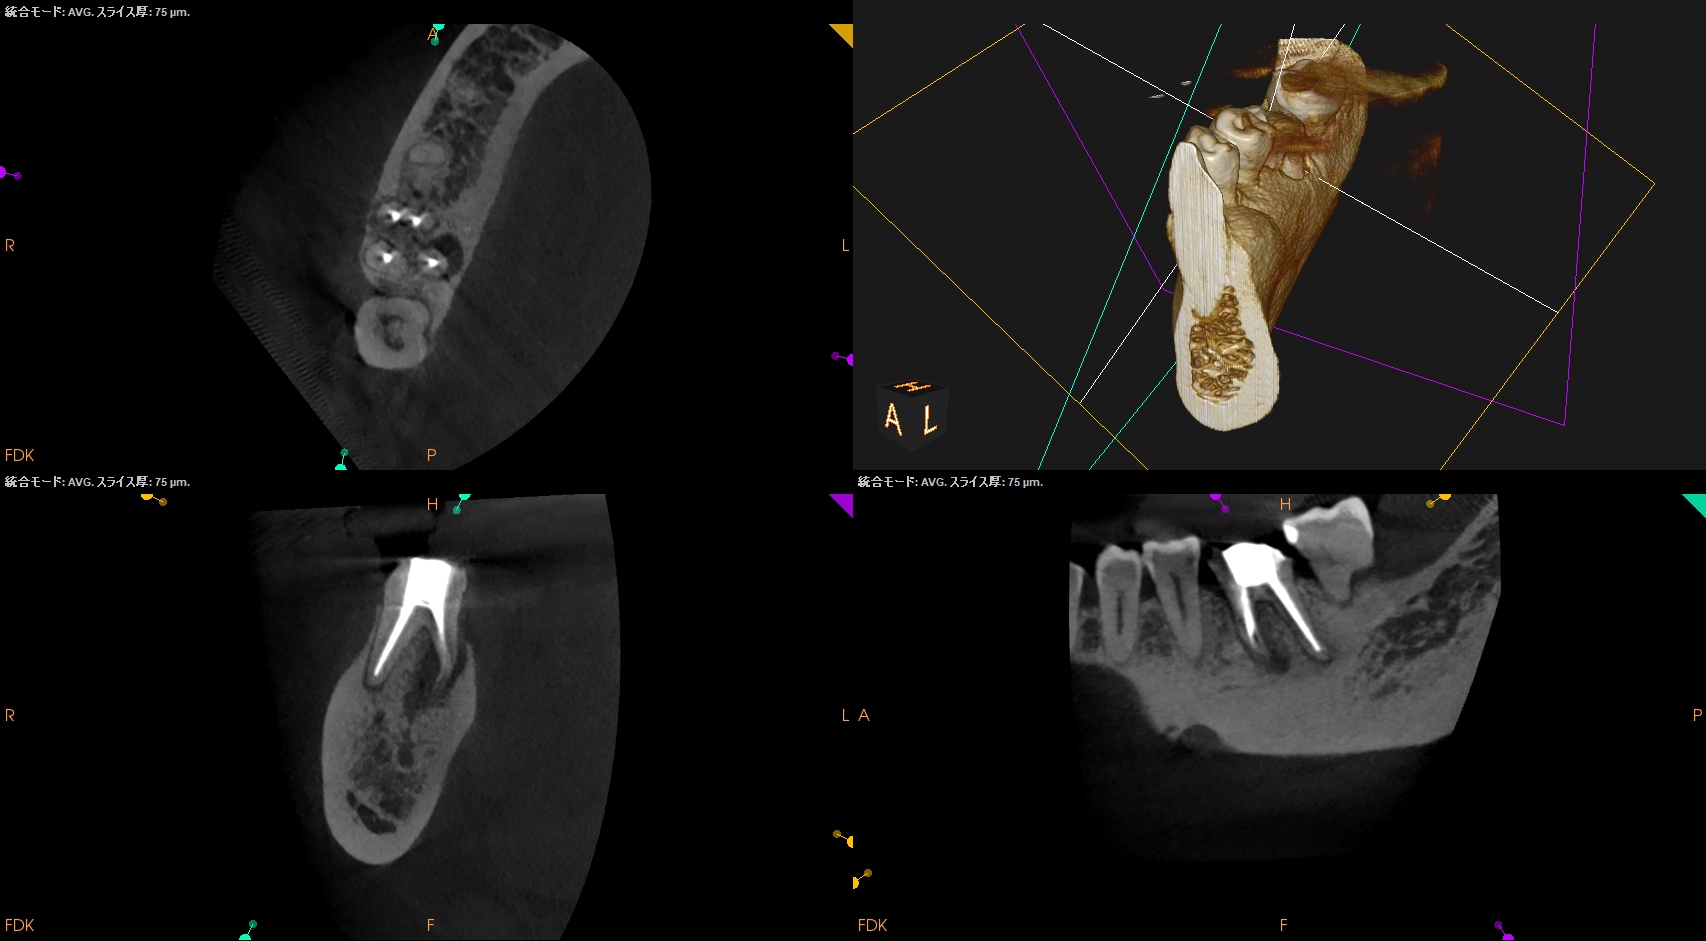

#30 Re-RCT 1yr recall(2026.3.10)

MB

ML

D

Radix

初診時と比較した。

病変は完治した。

このことから最終補綴もOKだし、経過観察も終診とさせていただいた。